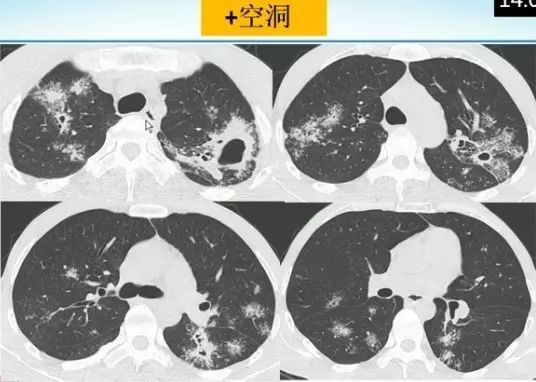

肺内“烟花征”,为活动性肺结核的CT表现之一。是结核经支气管播散并由多发小叶中央结节堆积而成,形态特征似烟花在空中散开。病理基础为细支气管及肺泡内干酪坏死性肉芽肿。

下文为解放军总医院放射诊断科赵绍宏教授课件分享,希望同行朋友们下次遇到类似病例,能够正确诊断。再次感谢赵教授的精彩讲解。